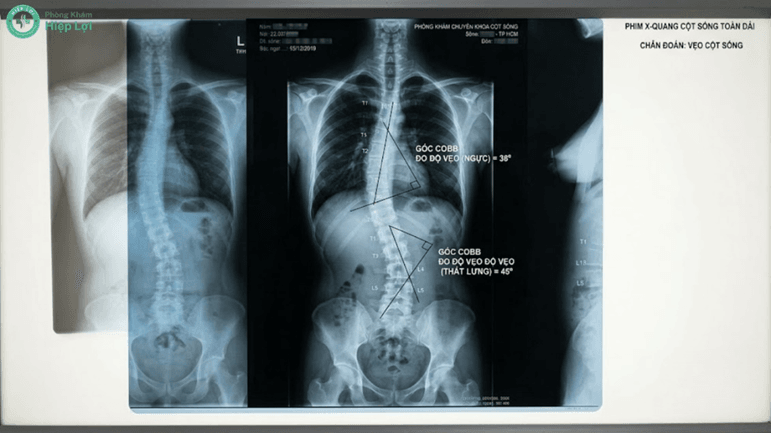

- Chụp X-quang toàn bộ cột sống (Tư thế đứng thẳng và nghiêng): Đây là "tiêu chuẩn vàng" giúp bác sĩ nhìn thấy toàn cảnh đường cong. Dựa vào phim X-quang, bác sĩ sẽ đo góc Cobb để xác định chính xác cột sống đang vẹo bao nhiêu độ.

Chụp X-quang toàn bộ cột sống là phương pháp bắt buộc giúp bác sĩ đo chính xác góc vẹo (góc Cobb) để đưa ra phác đồ nắn chỉnh phù hợp nhất.

Chỉ được chỉ định khi đường cong vẹo quá lớn (góc Cobb > 40-50 độ), độ cong tiến triển nhanh liên tục, người bệnh đau đớn dữ dội không đáp ứng với thuốc, hoặc bị chèn ép tủy sống gây yếu liệt chi dưới. Bác sĩ sẽ phẫu thuật giải ép thần kinh và dùng nẹp vít kim loại để cố định làm thẳng cột sống.